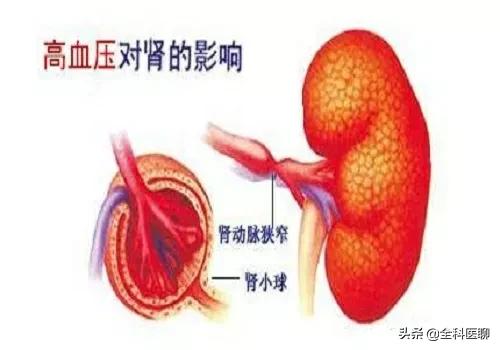

Pourquoi la microalbuminurie est-elle la première atteinte rénale de l'hypertension ? Le glomérule du rein étant en fait un ballon vasculaire, le sang de l'ensemble du corps est filtré par le glomérule pour produire l'urine. Lorsque le glomérule filtre l'urine, il y a une membrane de filtration et, dans des circonstances normales, des substances telles que les protéines ne peuvent pas être filtrées. En cas d'hypertension artérielle, l'augmentation de la pression artérielle endommage les vaisseaux sanguins et, bien sûr, les glomérules, de sorte que la membrane de filtration est endommagée et que les protéines s'échappent. Au début, il s'agit d'albumine de petit poids moléculaire, mais lorsque les dommages sont importants, des protéines de grande taille s'échappent également. Lorsqu'une plus grande quantité de protéines s'échappe, une protéinurie importante se produit et les analyses d'urine de routine révèlent la présence de protéines.

La relation entre l'hypertension et les reins est à la fois étroite et complexe, et les dommages causés aux reins par l'hypertension comprennent principalement : ① la néphrosclérose : au début de l'évolution des patients atteints d'hypertension essentielle légère et modérée, pendant une période assez longue, il n'y a pas de changements structurels et fonctionnels évidents au niveau des reins, seulement le spasme des petites artères rénales et l'affaiblissement de la fonction d'autorégulation rénale, comme la réduction de la capacité d'adaptation à des états non physiologiques tels qu'une charge élevée en sodium et une expansion volumique aiguë. Après un certain temps, en raison du spasme continu des petites artères rénales, celles-ci subissent une dégénérescence, un durcissement et un rétrécissement, et les unités rénales subissent une atrophie et une sclérose dues à l'ischémie, ce qui nuit gravement à la fonction rénale. L'hypertension primaire se manifeste d'abord par des lésions des tubules rénaux et des changements fonctionnels, le patient se manifeste par une nycturie accrue, les tests de laboratoire révèlent une petite quantité de protéines dans l'urine, principalement des protéines à petites molécules (la β2 microglobuline est un trait caractéristique), la gravité spécifique de l'urine est réduite et la capacité d'acidification de l'urine est diminuée. En général, l'hypertension primaire continue à se développer régulièrement et une petite artériosclérose rénale légère à modérée peut apparaître après 5 à 10 ans. ② athérosclérose de l'artère rénale : l'hypertension est un facteur causal important de l'athérosclérose, et l'artère rénale est un site privilégié de l'athérosclérose. L'artériosclérose rénale réduit le flux sanguin rénal, active le système rénine-angiotensine-aldostérone, provoquant une vasoconstriction, une rétention de sodium et une nouvelle élévation de la pression artérielle, formant ainsi un cercle vicieux. Environ 7 % des patients atteints d'hypertension primaire présentent une augmentation soudaine et progressive de la pression artérielle au cours de la maladie, qui se transforme en hypertension maligne. Lorsque la pression artérielle évolue vers une hypertension aiguë, une nécrose fibrinoïde des petites artères rénales se produit, et les reins sont gravement ischémiés, avec une détérioration rapide de la fonction rénale et une progression rapide vers l'urémie.

2) Quel est l'effet de l'hypertension artérielle sur les reins ?

Un choc prolongé d'hypertension artérielle entraîne, dès le début, une modification de la membrane filtrante mentionnée plus haut, c'est-à-dire une modification de la perméabilité, de sorte que certaines des plus grosses molécules, telles que l'albumine, qui ne pourraient autrement pas traverser la membrane filtrante, s'échappent de la membrane filtrante et que l'albumine puisse être détectée dans l'urine. Une pression artérielle plus élevée, pendant une période plus longue, agit sur les artères des reins, provoquant le rétrécissement de certaines des petites artères des reins, ce qui finit par réduire la quantité de sang qui atteint la membrane filtrante et, naturellement, la quantité d'urine produite sera également réduite, d'où une diminution de la quantité d'urine.